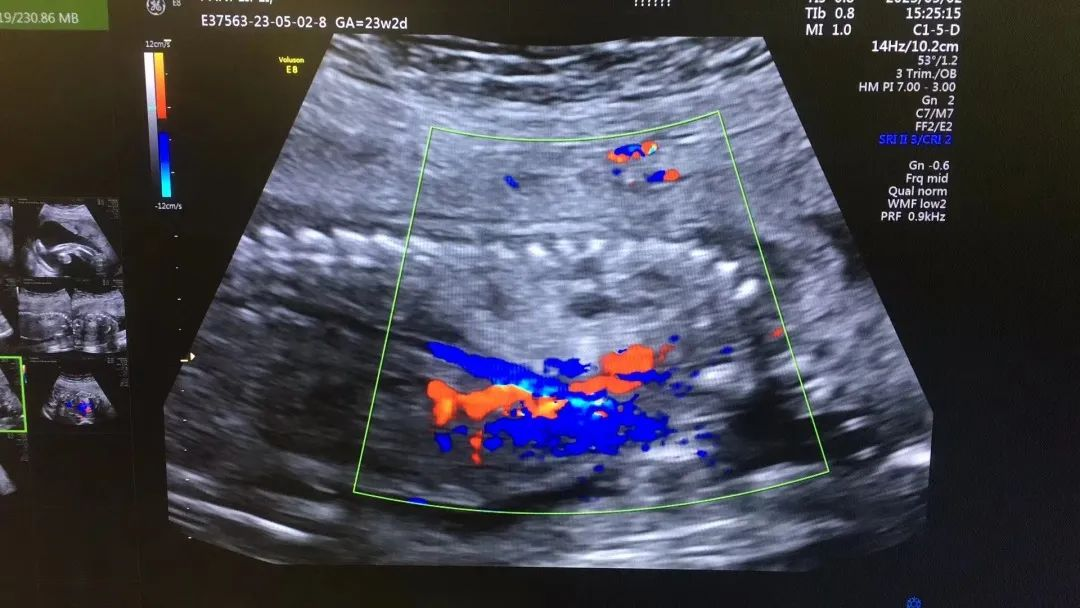

近日,我院超聲科醫(yī)生在給孕中期孕媽做四維彩超檢查時(shí),發(fā)現(xiàn)胎兒查出異常,孕媽想留下這個(gè)寶寶,陷入了兩難。

武漢的劉女士(化名),前幾個(gè)月剛懷上寶寶,全家都特別高興。懷孕23周+時(shí),劉女士在家人的陪伴下來(lái)到武漢仁愛(ài)醫(yī)院超聲科做了四維彩超檢查,當(dāng)醫(yī)生拿出檢查報(bào)告的時(shí)候,劉女士卻當(dāng)場(chǎng)傻眼了,原來(lái),在四維彩超的報(bào)告里,診斷出了胎兒右肺囊性腺瘤樣病變,她的心頓時(shí)揪了起來(lái)!

劉女士看到檢查結(jié)果后,擔(dān)心該病變會(huì)影響腹中寶寶的健康,考慮是否應(yīng)該終止妊娠。隨即,武漢仁愛(ài)醫(yī)院超聲科王娟主任為劉女士耐心地解釋?zhuān)?/span>“先天性肺囊腺瘤是一種肺組織錯(cuò)構(gòu)畸形,先天性肺囊腺瘤畸形病例約70%的腫塊大小較穩(wěn)定;約20%腫塊產(chǎn)前明顯縮小或消失;僅10%腫塊是進(jìn)行性增大。單純的先天性肺囊腺瘤(CCAM)無(wú)水腫的胎兒可以密切隨訪,在28周前接受連續(xù)超聲復(fù)查,CVR<1.6,一般超聲動(dòng)態(tài)監(jiān)測(cè)2~4周監(jiān)測(cè)一次,而對(duì)于CVR≥1.6的需要在28周前每周1-2次的超聲監(jiān)測(cè),防止出現(xiàn)胎兒水腫,直到分娩。”